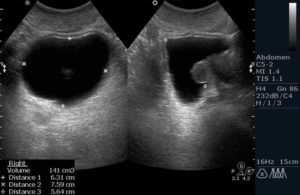

- Трансректально. Диагностирование проводят через анальное отверстие при помощи специального ультразвукового датчика. Данный вид позволяет определить наличие связи между патологиями предстательной железы и мочевым пузырем. С его помощью возможно контролировать количество остаточной мочи. Позволяет провести биопсию.

- Трансректальное исследование. Делается в положении на боку, исследуют орган с помощью введения датчика в прямую кишку. Методика предназначена для мужчин и девочек. Метод отличается высокой информативностью, по сравнению с трансабдоминальным.

Ультразвуковое исследование мочевого пузыря и простаты мужчинам выполняется в основном через переднюю брюшную стенку. Однако бывают случаи, когда необходимо использовать и трансректальное исследование.

- Трансректальное УЗИ выполняется реже. Показаний к нему несколько. Это ожирение, асцит, то есть наличие большого количества жидкости в брюшной полости, и при подозрении или уже имеющихся опухолях предстательной железы и мочевого пузыря.

- Трансректальное УЗИ простаты и мочевого пузыря, подготовкой отличается, но также потребует наполненного мочевого пузыря. Перед таким исследованием потребуется очистить прямую кишку. Применить можно слабительные средства, специальные свечи или микроклизмы. Отличается и методика проведения, о которой речь пойдет далее.

- Трансректальное УЗИ мочевого пузыря и простаты выполняется уже другим датчиком, который адаптирован для исследований через прямую кишку. Преимущества такого исследования в том, что датчик находится в непосредственной близости от мочевого пузыря и все, что их разделяет — стенка прямой кишки.

Таким образом, если имеется опухоль предстательной железы, ее можно будет рассмотреть гораздо лучше, нежели при трансабдоминальном УЗИ.